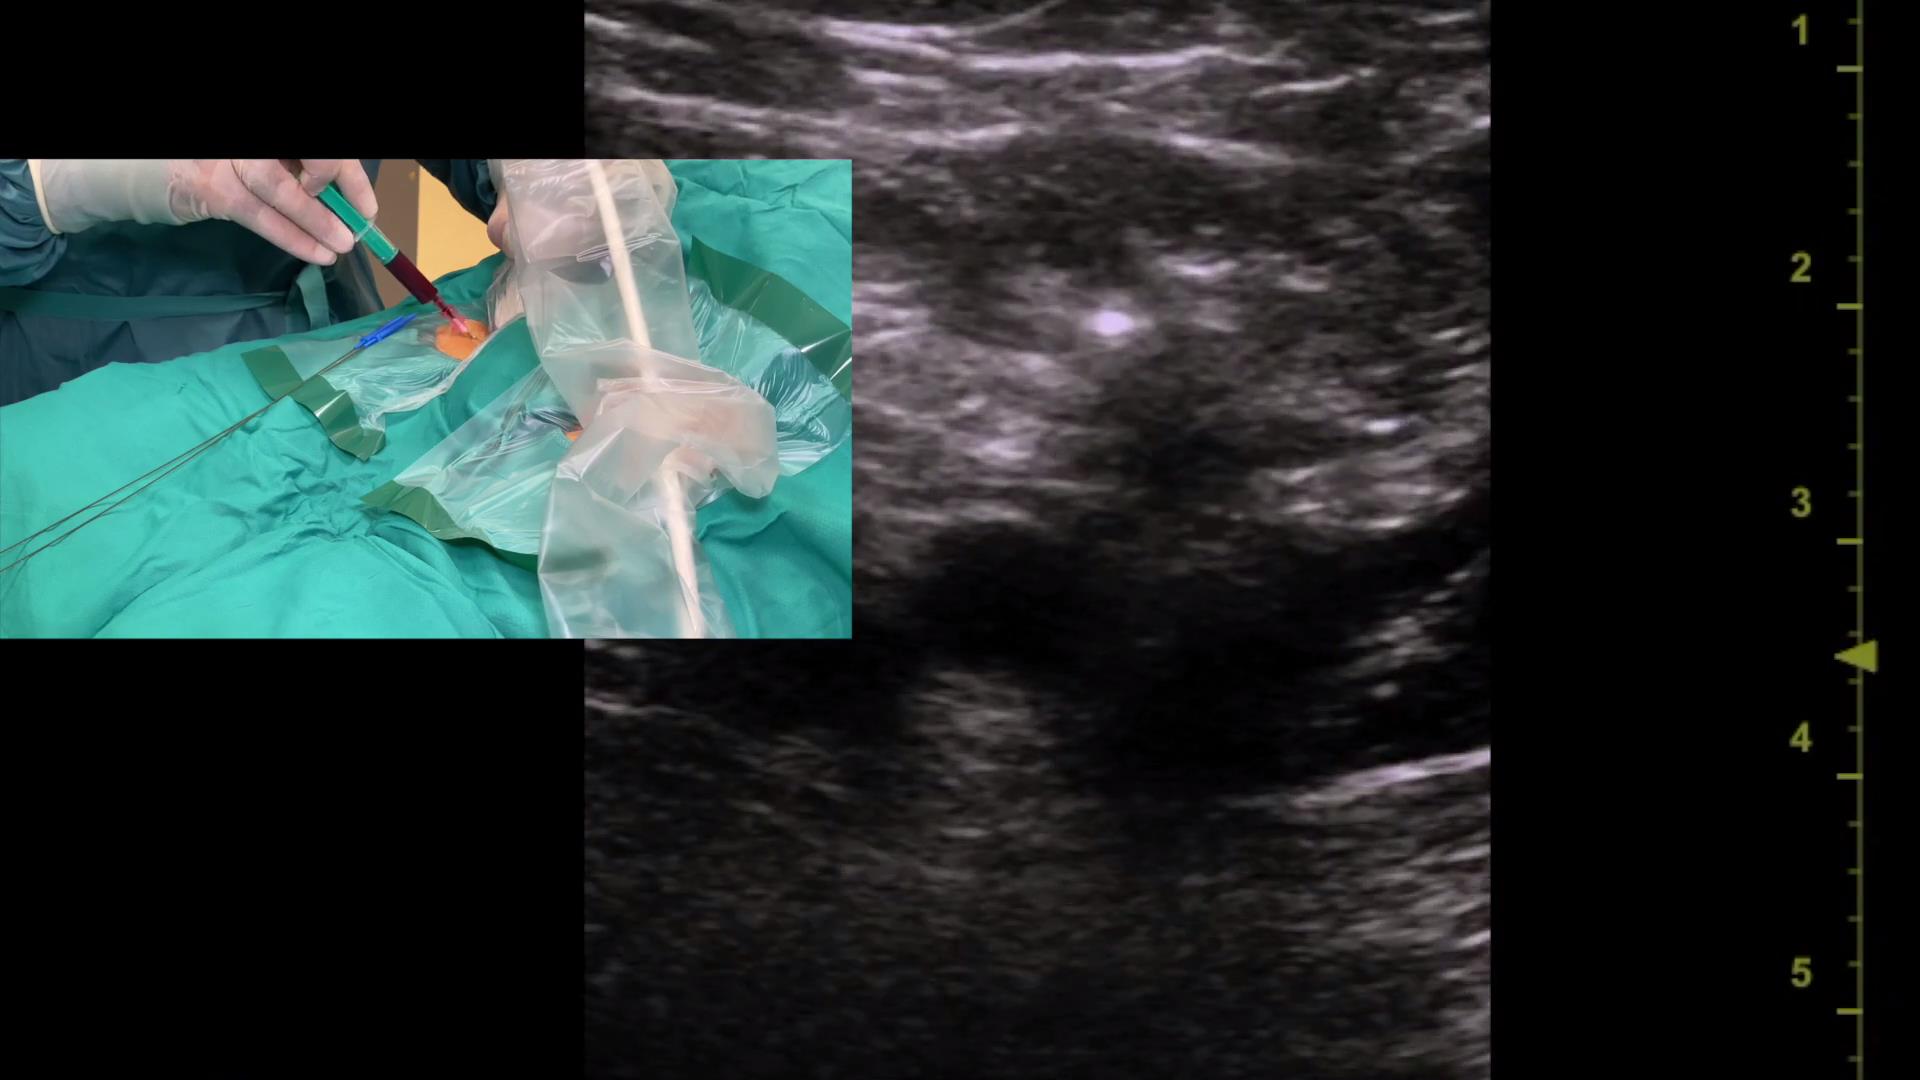

超声引导下锁骨下静脉穿刺置管

318 #锁骨下静脉穿刺